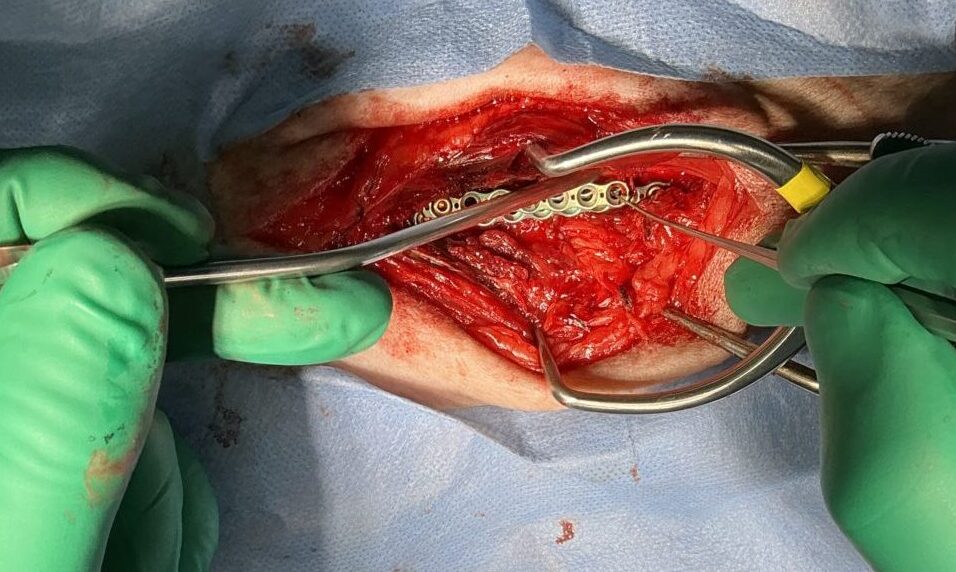

10歳のワンコが後肢フラツキの精査のため、かかりつけの動物病院より画像診断と治療のために紹介受診されました。CT/MRI検査では第3腰椎の左側から脊柱管内に重度に浸潤し、脊髄の90%以上を圧迫する占拠性病変が確認されました。また椎体にも骨融解像が確認されました。姑息的ではありますが、腫瘍摘出により除圧することで神経学的機能回復に期待することと、今後の病期の進行に伴い椎体の不安定性が懸念されたため、2.0mmのTitanium Locking Plateを2枚用いて部分的にスタッキングさせると同時に4本のLocking Screwを用いて椎体固定術を実施しました。脊柱管内に浸潤し、脊髄を圧迫していた腫瘍はほぼ完全な摘出が可能となりました。術後すぐに歩行可能となり、良好な機能回復が得られています。今後は摘出した腫瘍の病理検査により追加の治療を決定します。